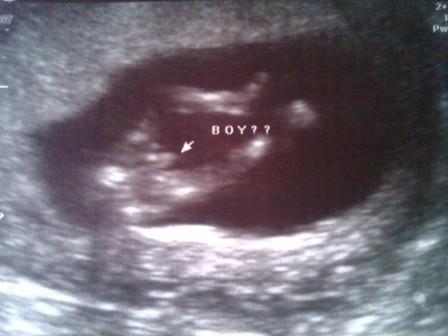

12 week sono...Interesting appt with pic!

So I went for my 12 w sono today (I'm 12w3d). The baby looked great and measured ahead another 2 days although the sono tech told me to keep my original due date. The tech was looking at the baby from tons of different angles and then she got a shot of the underside of the baby. At the same time both DH and I saw what looked like male genetalia! And the sono tech said...yup! That could be a boy!!!! She of course prefaced that with telling us that it's so early on and that it was a 60% chance of it being right....and the sono could read differently later on. I posted the pic below to get your thoughts!

They also did the finger prick...How long did you have to wait to get your results and did you wait to tell people until after you got the results back? We are dying to tell people (and it's getting harder to hide!). Thanks! Let me know your thoughts! Image Attachment(s):

Glad your appt went well and that DEF looks like a !!!! It took 1 week for me to get my results.

Oooh, that def looks like a boy to me!!

That def looks like a !!!! Great pics! We got the results a week later.

well if that's a girl you got issues....LOL

i would definitely say

Great pics!! Looks like it could be a boy

great pictures your sono tech got!! looks like boy!

I don't think boy parts actually develop until weeks 11 or 12 and they don't move down until a week or two after that... but you never know...

Crashing, but wanted to say that I totally think you're having a little boy. We got a very similar shot on our 12 week sono, we we just knew it and it turns out he was a .